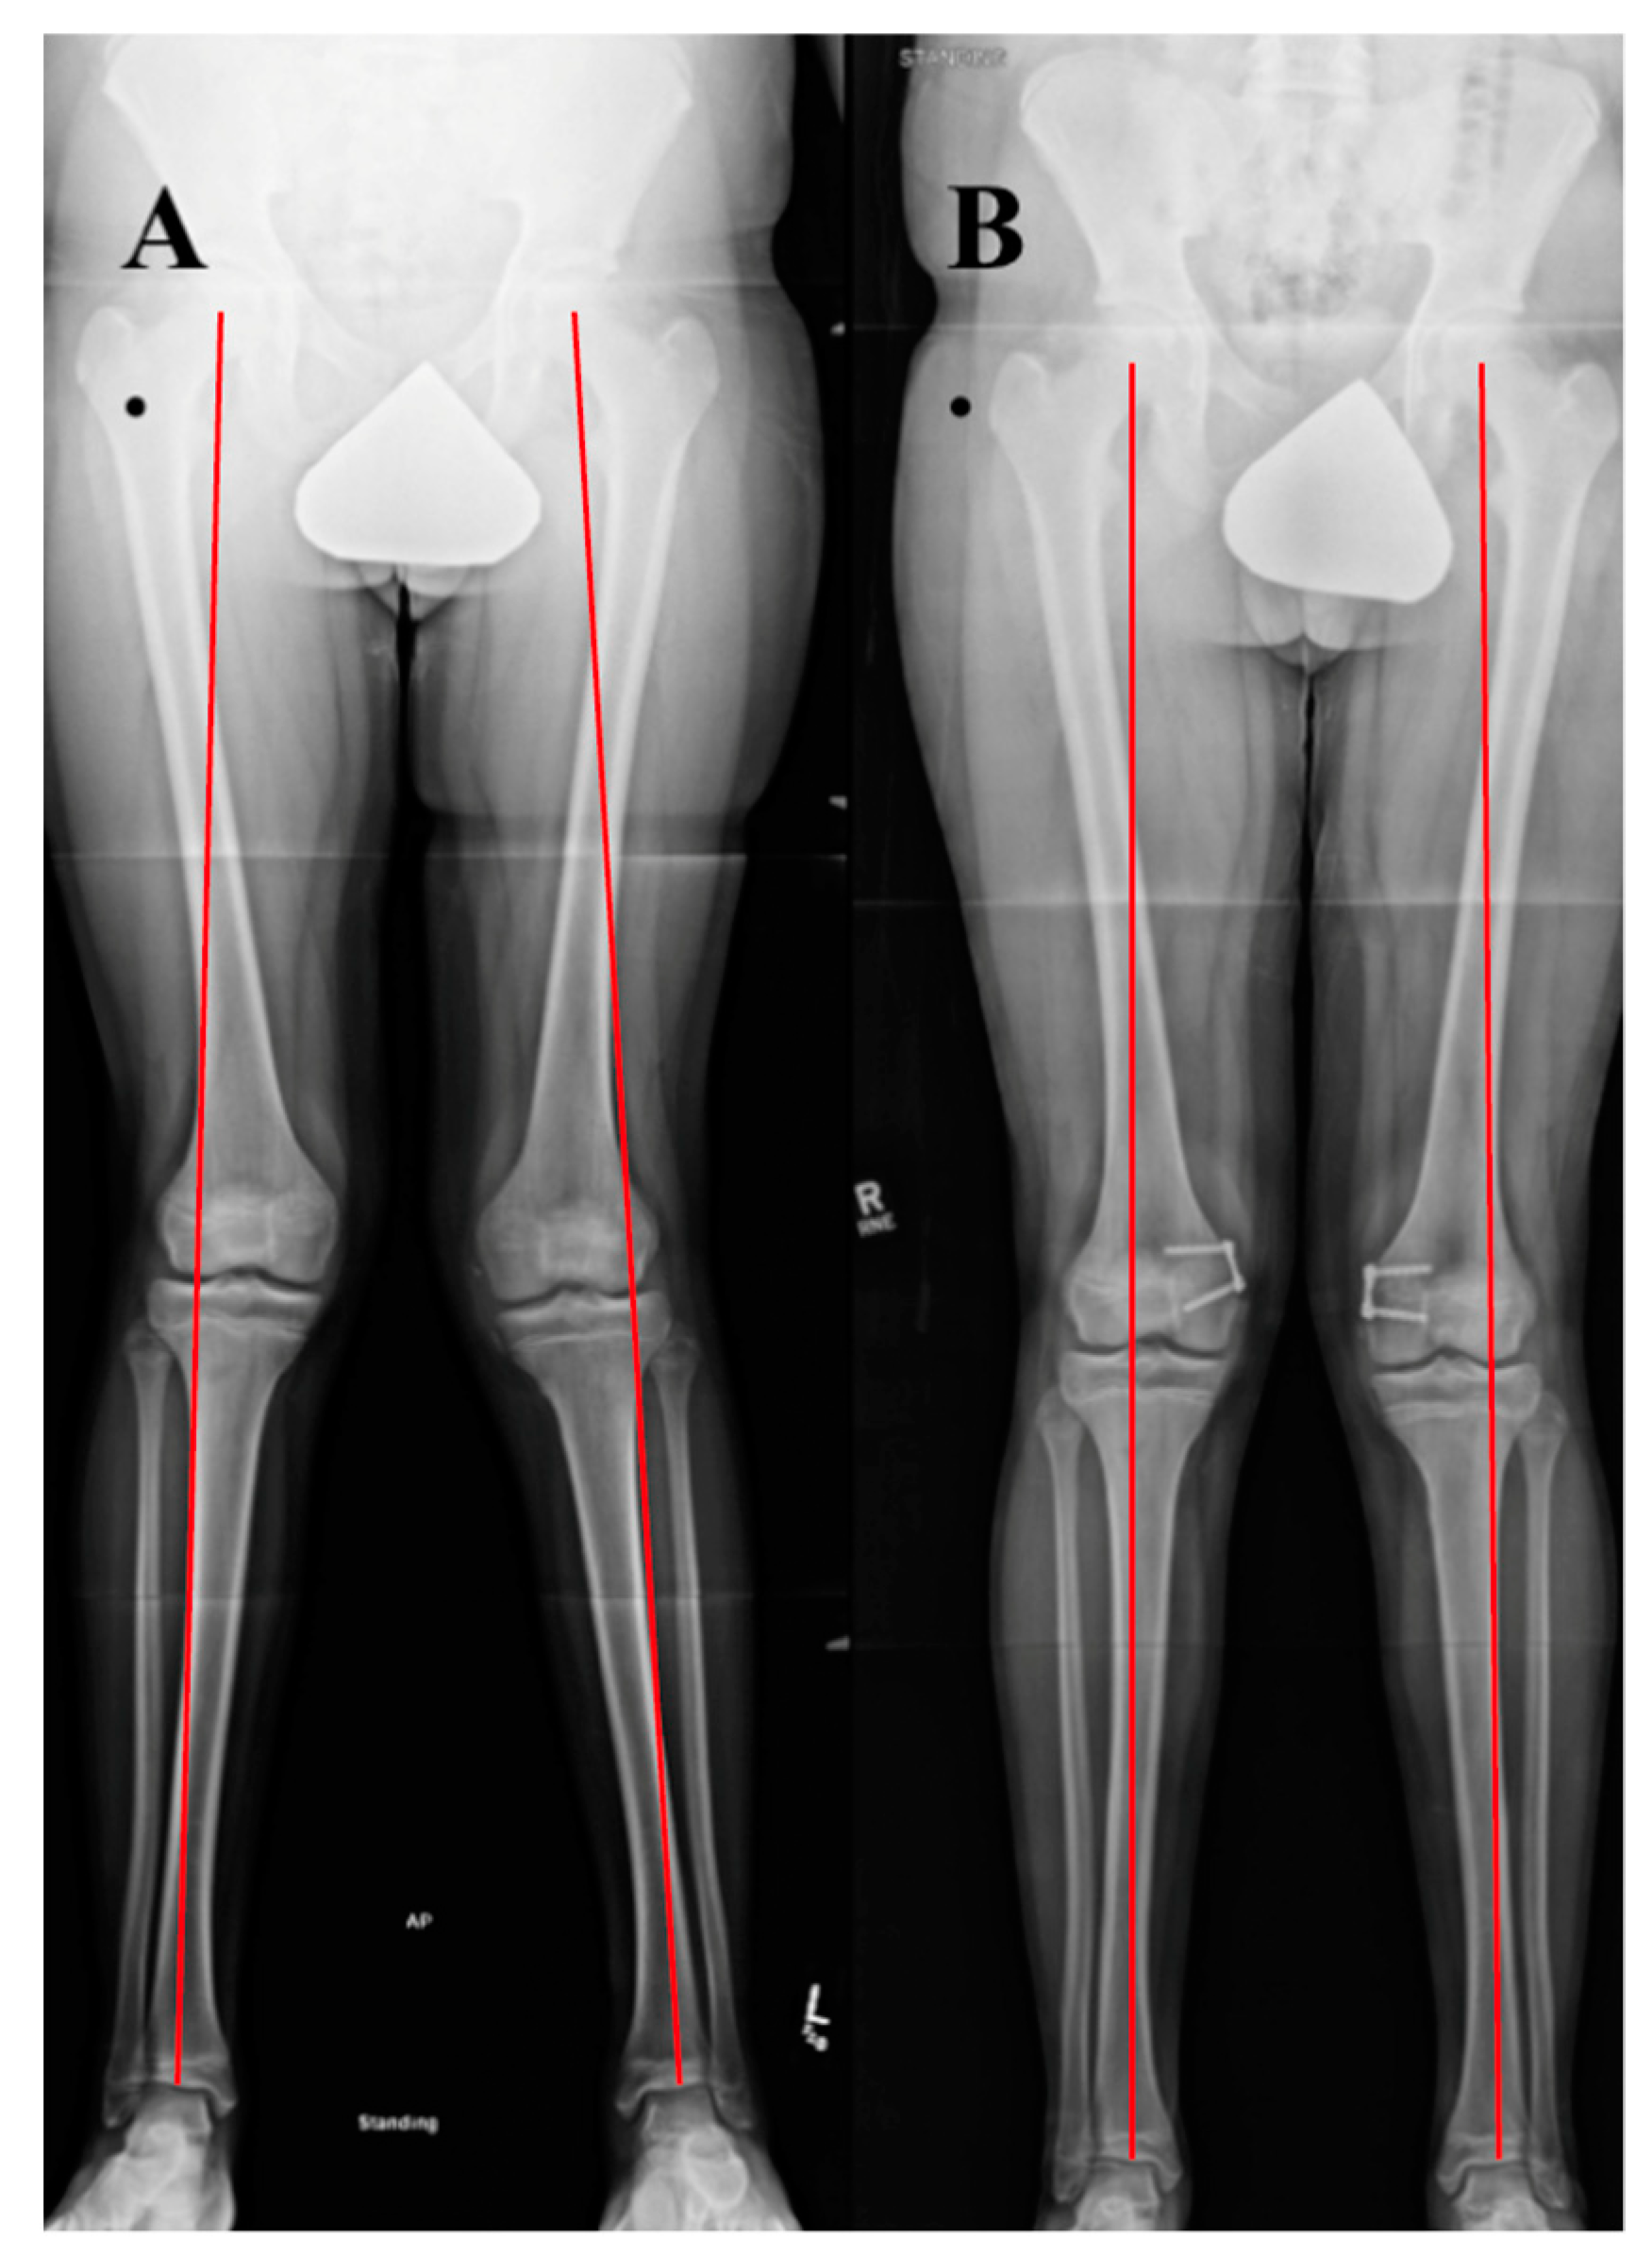

3.1. Coronal Plane Malalignment